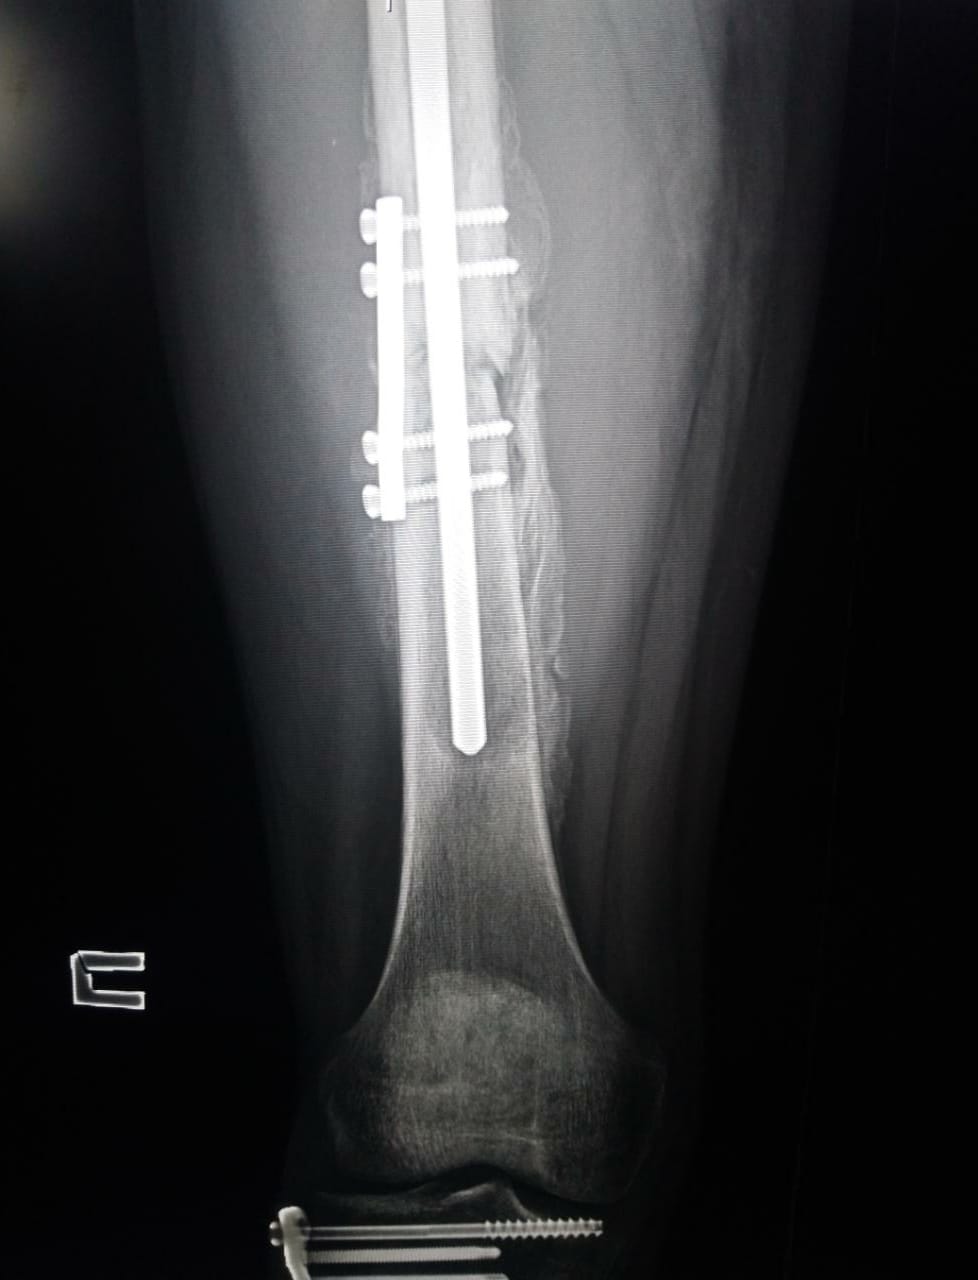

Пример оперативной фиксации диафиза бедра

Согласно врачебной практике из доступных источников известно, что период восстановления после подобной травмы с полной нагрузкой на кость - до 3-4 месяцев.

Учитывая современные медицинские технологии в спорте, восстановление нагрузки при своевременном оперативном вмешательстве с установкой фиксирующего железа возможно уже через 4-5 недель. Восстановление костной ткани начинается в период не ранее 14 дней с момента проведения операции, первая стадия длится не менее 28 дней.